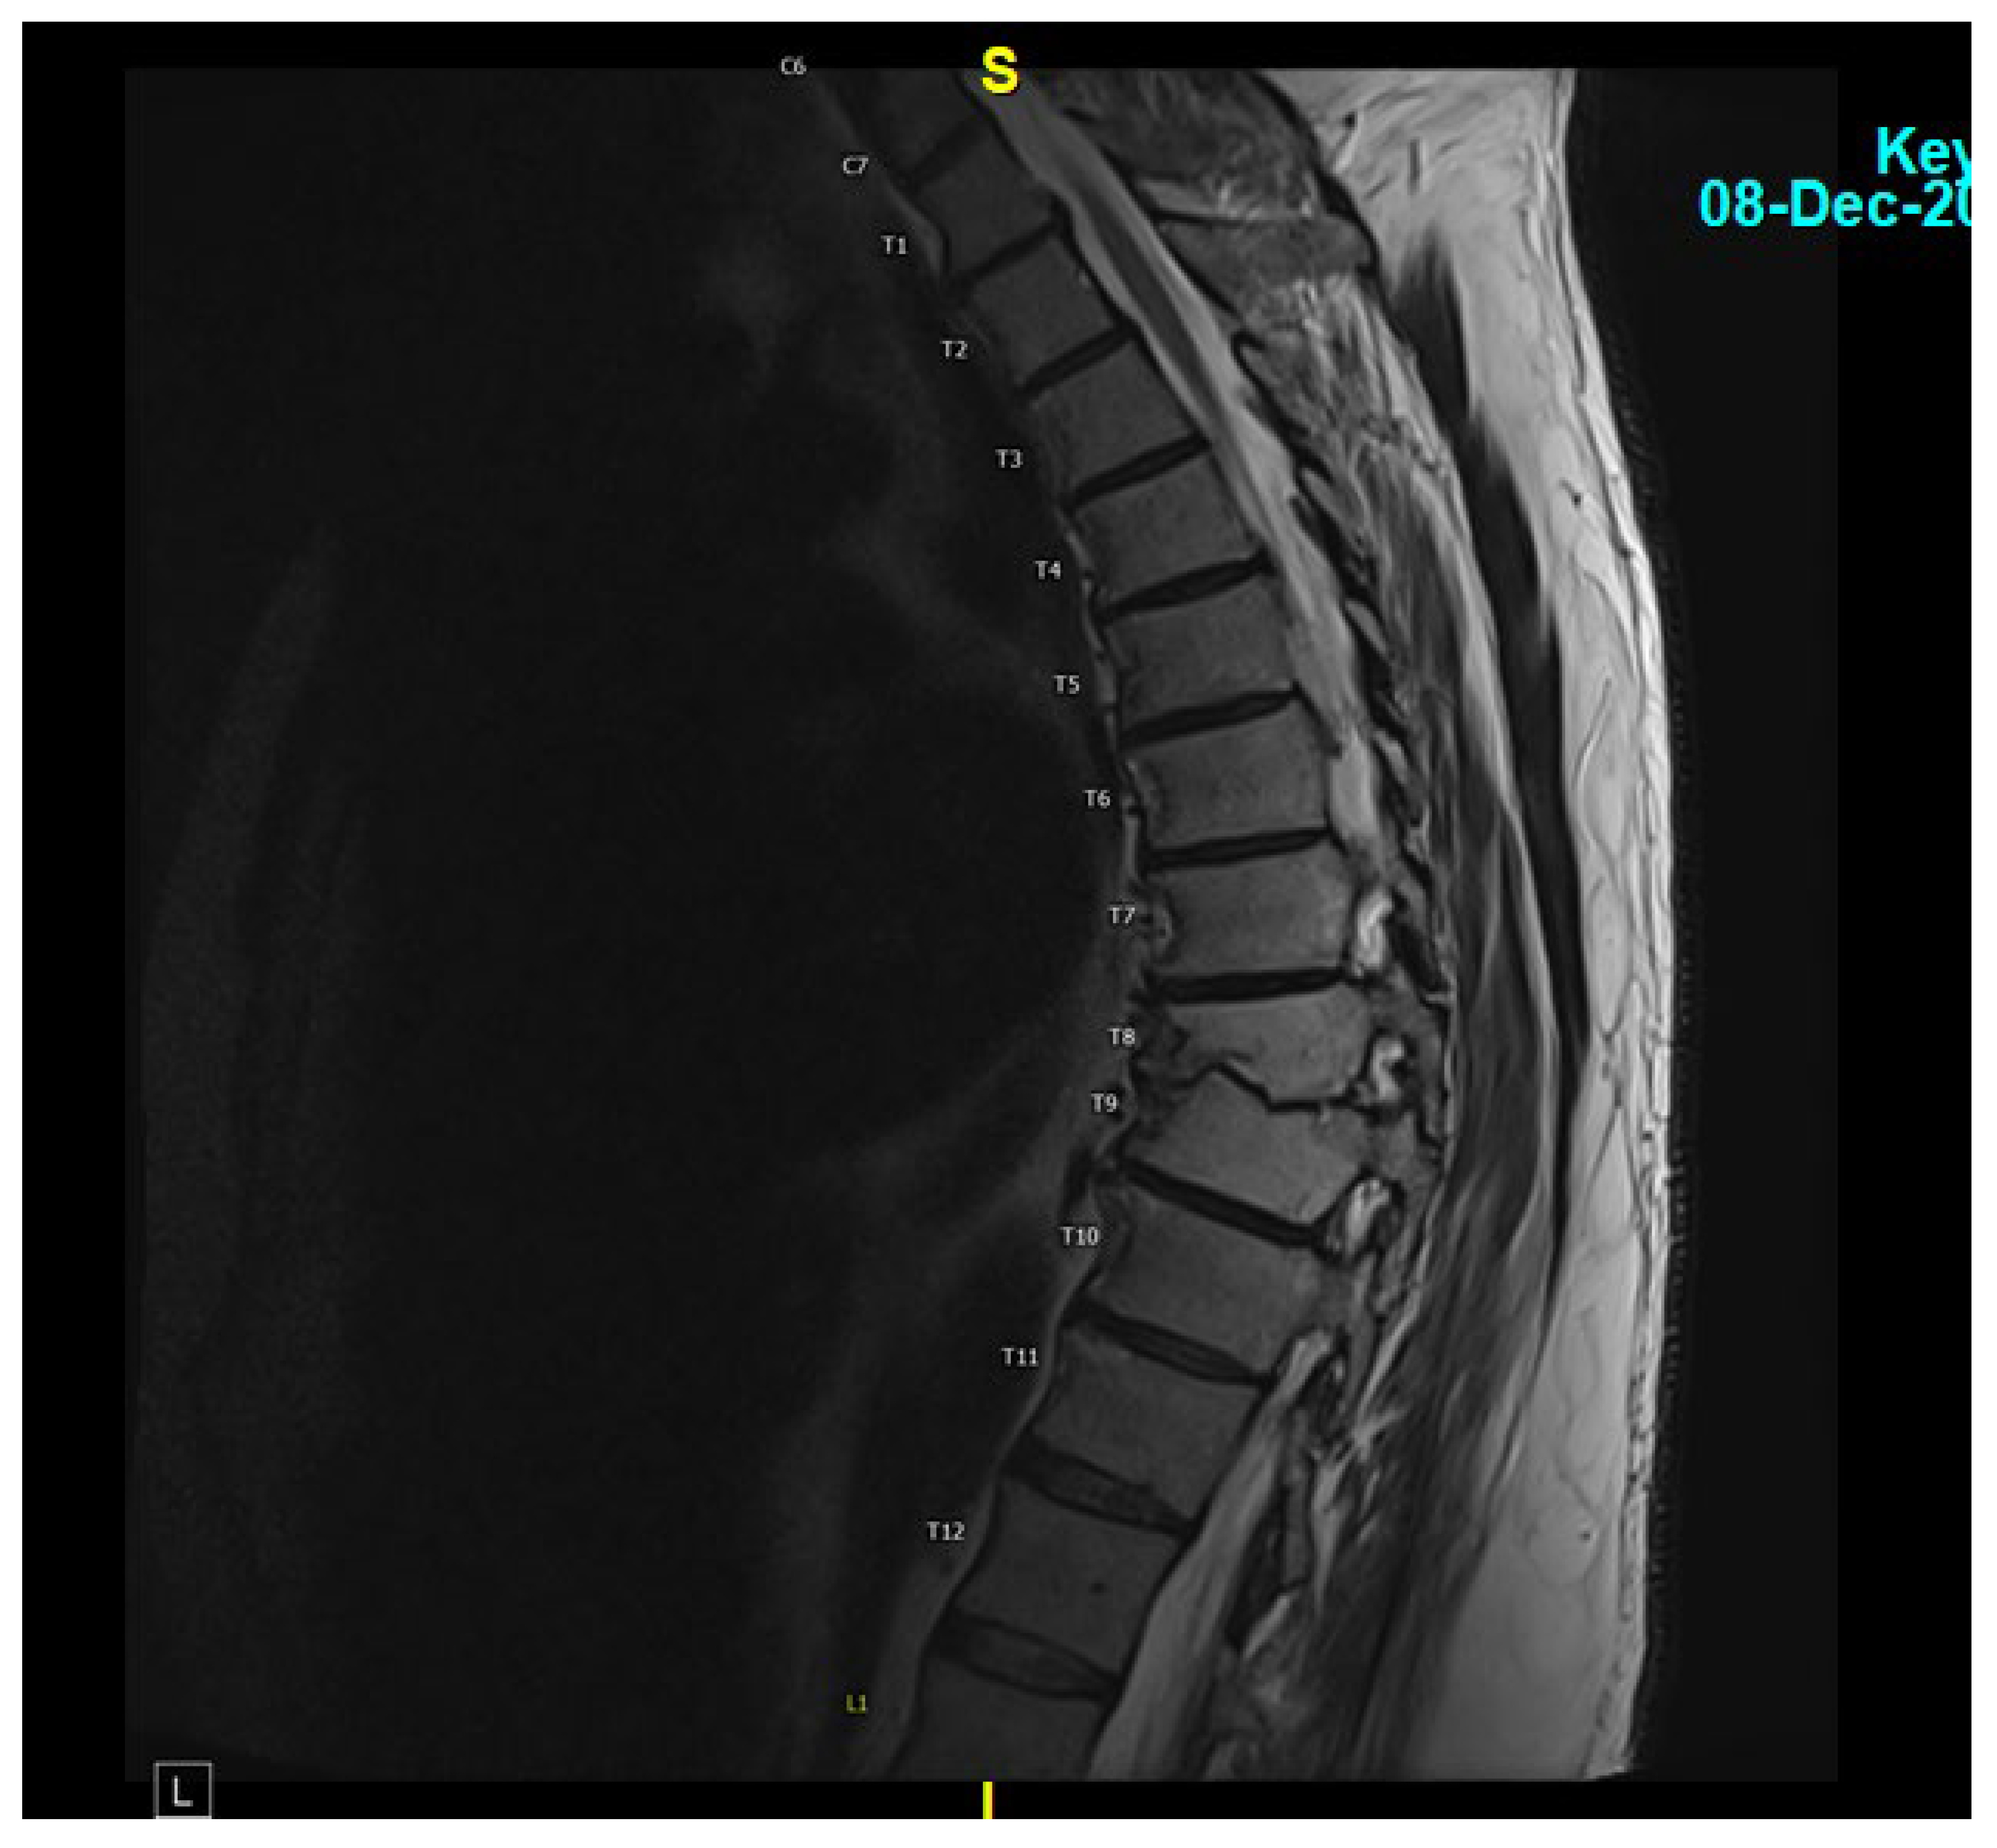

A 62-year-old male with hypertension, type 2 diabetes, atrial fibrillation (on Eliquis), and an L5-S1 spinal fusion 16 years prior developed fever and back pain on 12 May 2023. He contacted a telehealth provider, who ordered a CT scan of the abdomen and pelvis to evaluate for diverticulitis. This imaging demonstrated no diverticulitis but evidence of T8-T9 vertebral osteomyelitis. He was subsequently hospitalized for 8 days, during which he underwent an MRI of the thoracic and lumbar spine with and without contrast, which showed a T8 vertebral fluid collection and diskitis (Figure 1). C reactive protein was 7.70 mg/L with an erythrocyte sedimentation rate of 16. He underwent a CT-guided biopsy of the impacted vertebra and disc. Stains and cultures for bacteria, mycobacteria, fungi, and histopathologic evaluation performed on these specimens were negative. Because of concern for Staphylococcal (Coagulase negative) infection and convenience of administration, he was discharged on an empiric 6-week course of IV daptomycin 800 mg per day (started on 17 May 2023 and completed on 5 July 2023). His CRP normalized to <0.2 mg/dL at the end of treatment. Despite this treatment, his back pain worsened, for which he was prescribed hydrocodone/acetaminophen (Norco) and a muscle relaxer, metaxalone.

Figure 1. MRI thoracic spine with and without IV contrast revealing small T8 fluid collection and possible diskitis T8-T9.